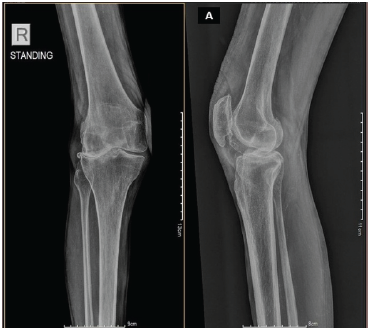

Gouty Arthritis Versus Chondrocalcinosis in a Stiff Knee, A Diagnostic Dilemma – A Case Report

Vineet Thomas Abraham , Muni Srikanth , Kalyan Deepak Sreenivas , Elandevan Gunasekaran , Vignesh Chandrasekar , Aditya Sharma

………………………………p.236-239